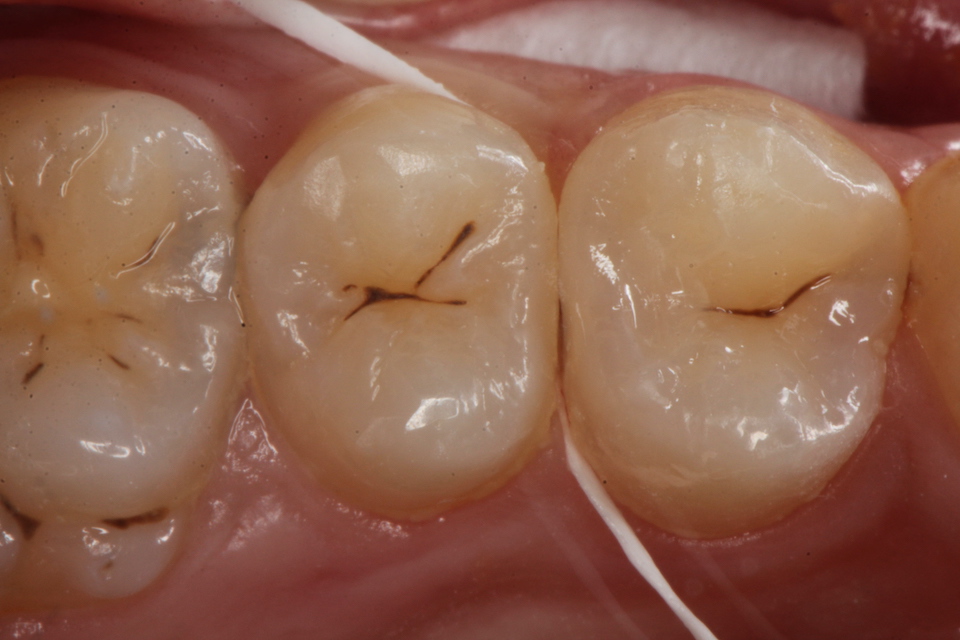

下顎7番の頬側歯茎部カリエスの原因 2025.06.04